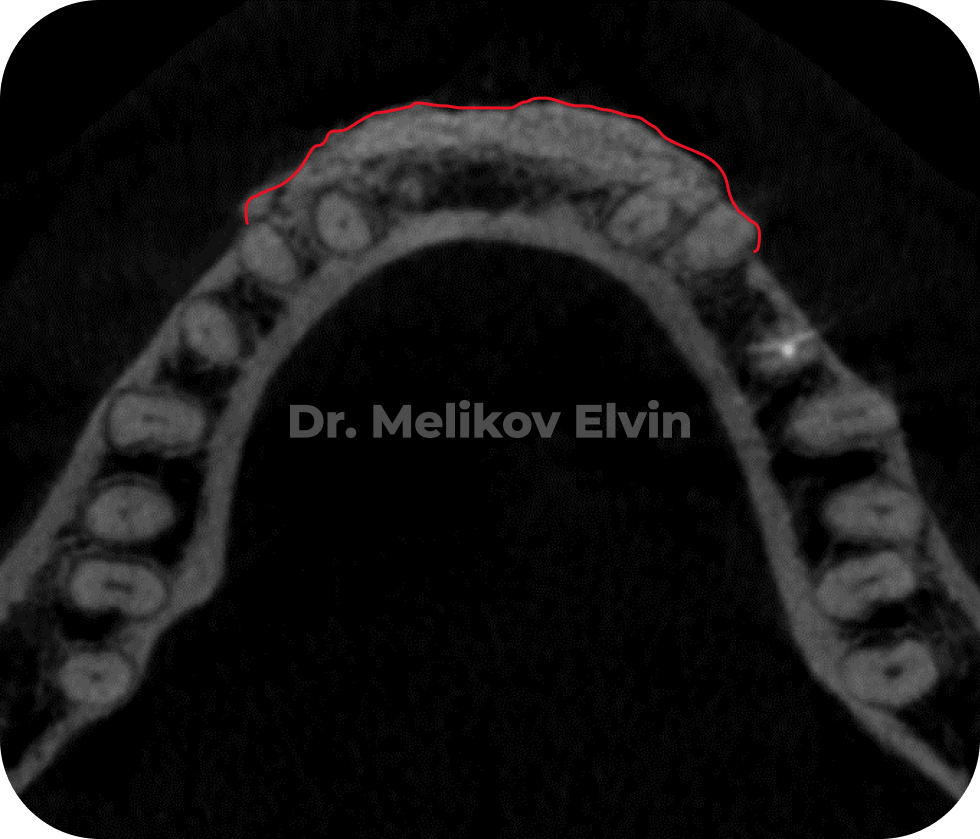

После костной пластики на верхней челюсти

На снимках можно увидеть воссозданный объём наружной кортикальной пластинки в проекции корней зубов.